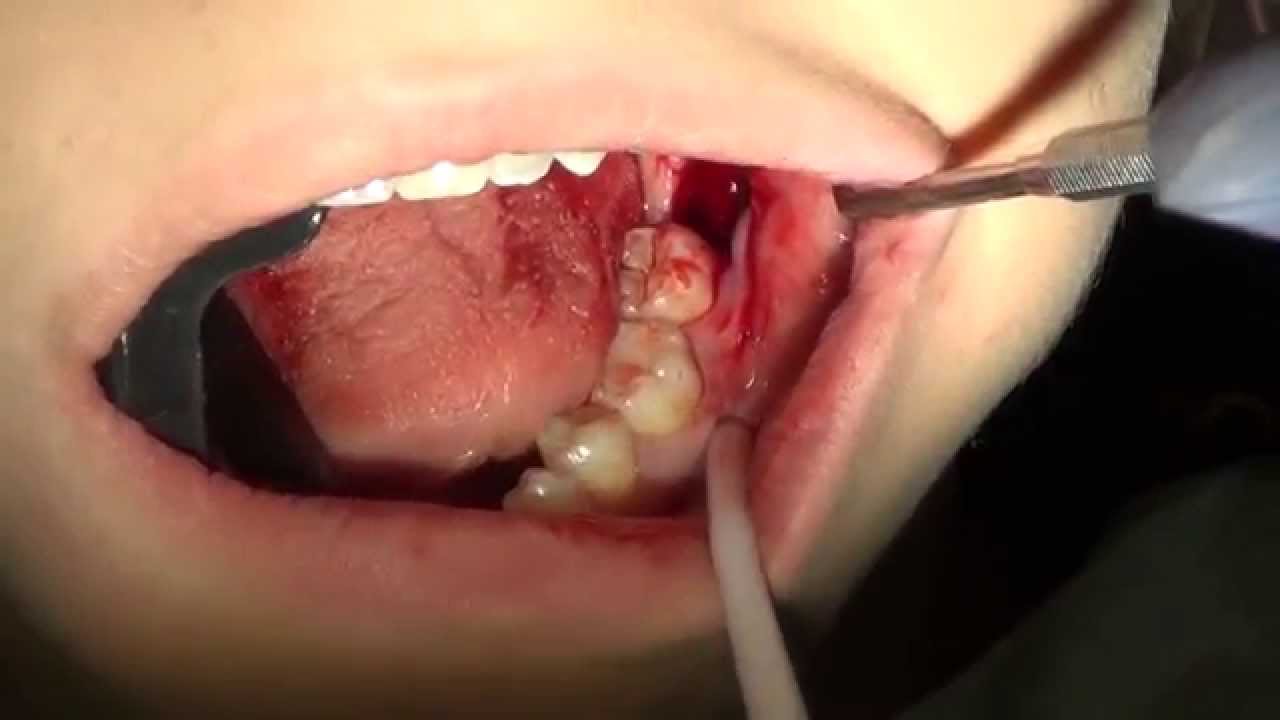

在這些情況下,你應該要拔智齒:牙齒完全藏在牙齦下,不能生長出來,破壞相鄰牙齒的根部;難以清潔,積累細菌;沒有充足空間,傷害到其他牙齒;智齒四周感到痛楚;智齒附近軟組織常常受感染;腫瘤形成;牙齦發炎;相鄰牙齒或智齒蛀牙;沒有對咬牙等等。

如果你有定時看牙醫,也有做過X射線檢查的話,其實是可以不用拔掉健康智齒的。不過在這種情況下,您要先提前了解可能發生的問題,像如果未來有不正確智齒生長的話,需要做手術拔掉它。牙醫也建議,如果要拔智齒,應盡快去做。因為25歲以後,骨骼組織成形,會使牙齒更難拔除,組織癒合得更慢。